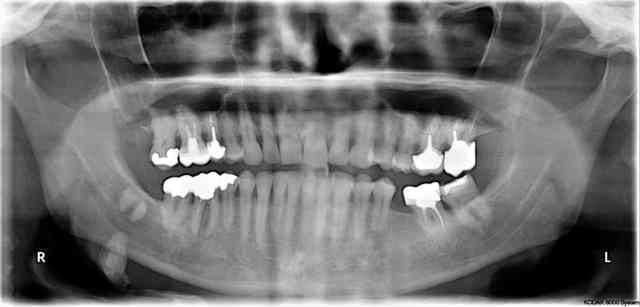

J ai deux panoramiques en 2013 et 2009 avec une meme image radioclaire en dehors de la mandibule. Est ce une glande salivaire?

Cette image peut faire penser soit à une calcification d'un insertion musculaire, soit effectivement à une calcification intra glande salivaire (parotide...)

Je dirais aussi que c'est dans la parotide. Et je prescrirai une TDM.

C'est certainement une calcification de la sous max. A contrôler par une échographie et interrogatoire clinique.

Accessoirement il semble présenter des calcifications intra parotidienne droite.

1. lithiase ou calcification de glande submandibulaire mais c'est gros pour une lithiase asymptomatique

2. ganglion lymphatique calcifié suite à un ancien processus infectieux

3. possible ostéome car j'avais déjà vu un cas tout à fait transposable

comme c'est calcifié je ferai de préférence un scanner avec injection +/- IRM vis-à-vis des tissus mous et de la composante calcifiée si vraiment fallait investiguer.